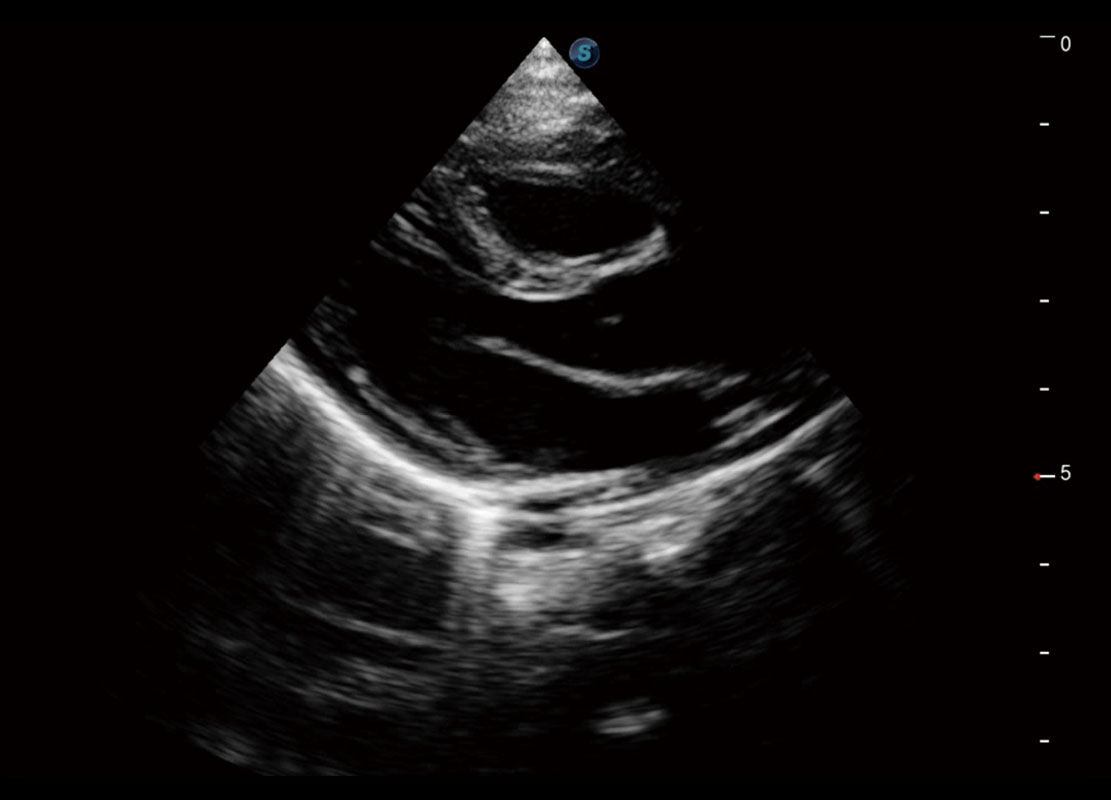

中晚孕筛查

P60提供简单易学易用的高端诊断工具,为您中晚孕筛查提供快速清晰的解剖信息。

S-Fetus能够助您在实时扫查过程中自动识别标准切面、自动测量并录入报告。一个按键,即可快速、高效地获取胎儿生理指标,简化您的产科检查操作。